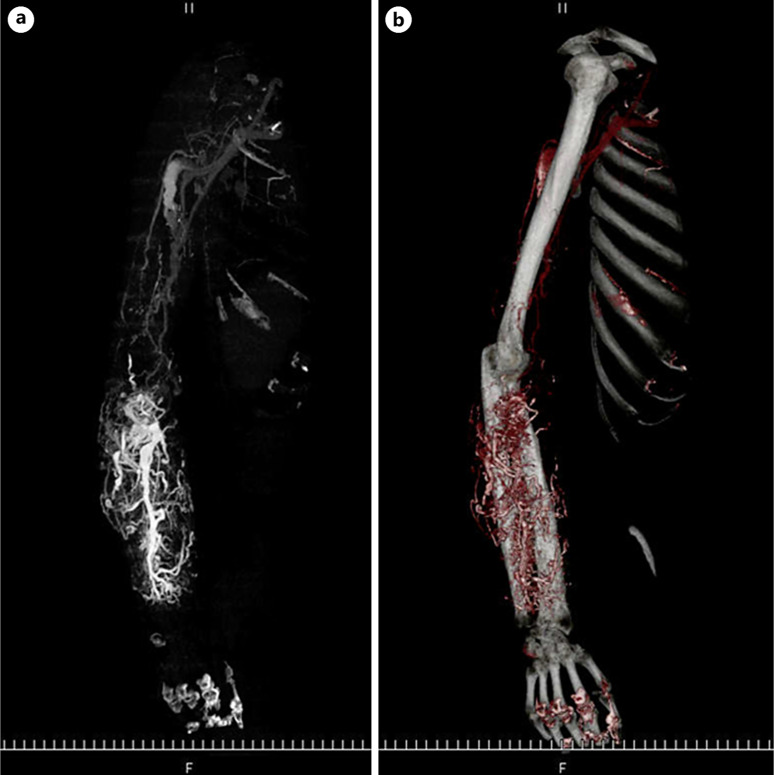

Case presentation: A 74-year-old man was admitted for the evaluation of liver tumors. His medical history included a chronic, intractable idiopathic right forearm AVF, for which he had undergone multiple surgical interventions. Abdominal EOB-MRI revealed multiple small focal lesions across both liver lobes during the hepatobiliary phase, indicative of multiple HCC, and liver biopsy confirmed early-stage HCC. Considering the potential presence of additional vascular anomalies similar to the forearm AVF, local hepatic artery chemoembolization was performed. Since there is still insufficient discussion about the systemic administration of angiogenesis inhibitors to patients with vascular abnormalities such as AVF, we discuss the treatment options for HCC with AVF, including its strategies in the progressed HCC stage.